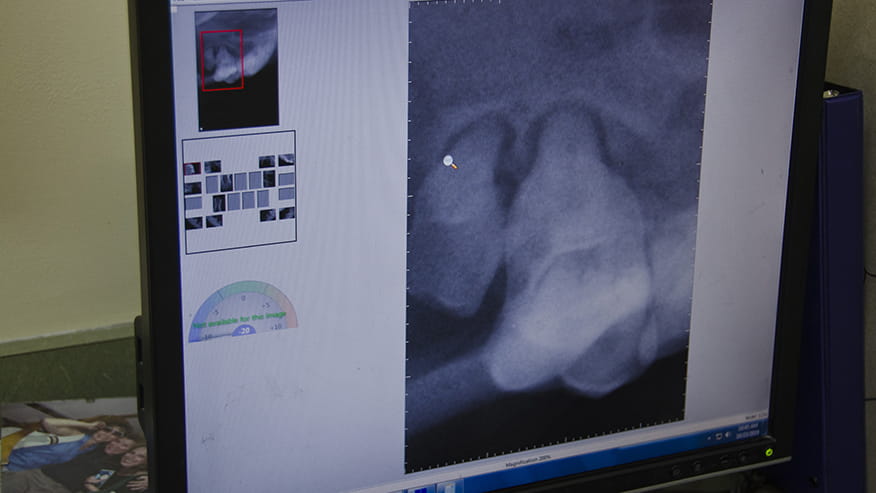

Our hospital offers dental radiographs (x-rays) as part of our dental care services. In the course of dental treatment, specially designed dental radiology equipment allows your veterinarian to view structures that lie below the gum line. The location of tooth root infections, the extent of periodontal bone loss and the identification of bone cysts and tumors can be identified using dental x-rays.... Read more